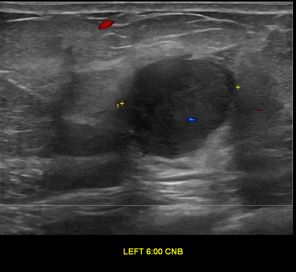

상기환자는 외부검사 이상소견으로 내원하신 50대중반 여성분으로 의심스러운 좌측혹

조직검사 시행해 유방암으로 진단되었습니다